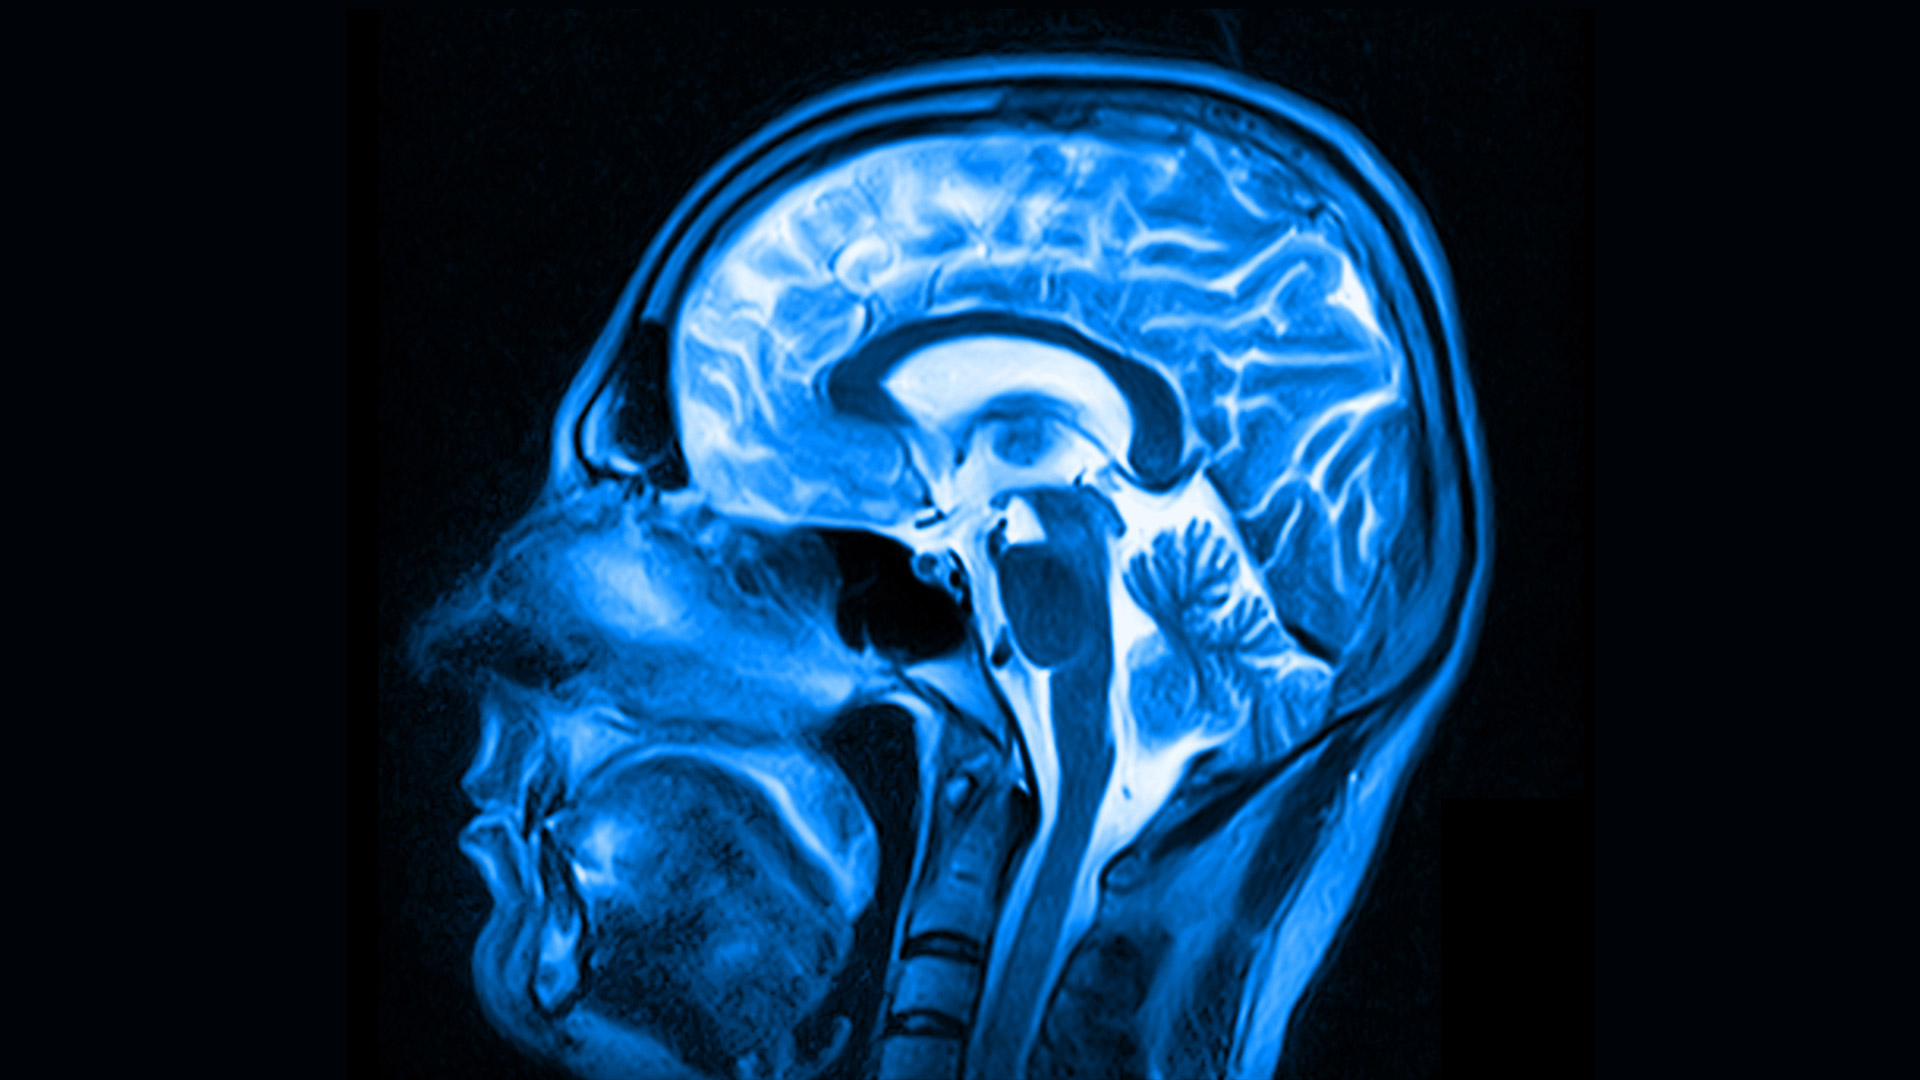

Исследование японских ученых, опубликованное в журнале Human Brain Mapping, показало, что различия между отключением сознания и вышеуказанными состояниямивидны на МРТ. То есть, когда разум «опустошен», характер мозговой деятельности иной. Более того, участники этого исследования могли намеренно войти в состояние опустошения сознания.